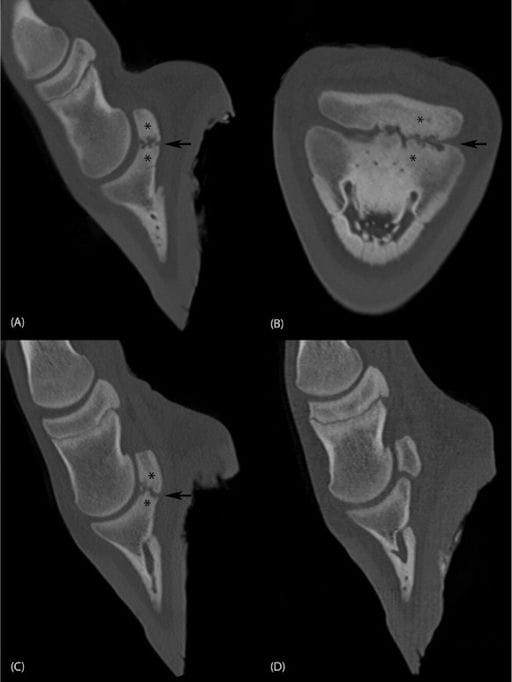

Multiplanar reconstruction (MPR) fan beam CT images with a bone algorithm of the distal limb. (A) Parasagittal and (B) dorsal plane of the left hind limb, lateral is to the right. Marked subchondral hypoattenuating bone lesions surrounded by a hyperattenuating area (asterisk) are visible at the level of the lateral articulation site of the navicular bone and the distal phalanx. Small, well-defined, tubular hypoattenuating structures within the distal phalanx are visible as focal round regions in (B), likely representing vascular channels. There is an altered shape and elongation of the distal navicular bone and proximal distal phalanx, resulting in focal deformation and narrowing of the plantar joint space (arrow). (C) Parasagittal plane of the right front leg shows similar changes compared with the left hind (A), with a small intra-articular mineral body. (D) Parasagittal plane of the left front limb at the same level as (C), showing normal morphology.

Radiographs revealed focal osteolysis and irregular bony proliferation at the palmar/plantar margin of the distal phalanx adjacent to the navicular bone. Postmortem CT identified bilateral, focal, severe osteolytic and osteoproliferative changes confined to the distal navicular bone and proximal distal phalanx, causing deformity, joint space narrowing, and partial bony fusion. Multiple additional small osteochondral defects were observed in other joints. Histopathology showed irregular articular surfaces, fibrous tissue infiltration, trabecular thickening, and secondary osteosclerosis and myelofibrosis, consistent with advanced focal joint disease but without an identifiable primary cause.